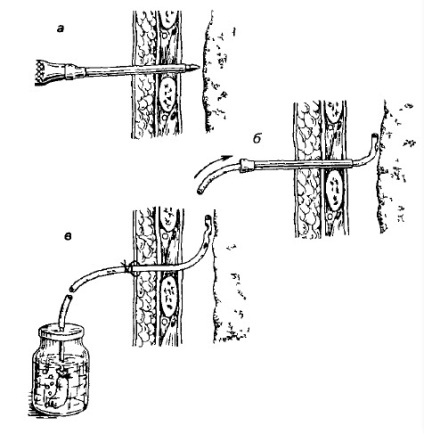

Amikor jelenlétében mellhártyaizzadmány meghatározott és nem kétséges elvégzéséhez szükséges sebészi beavatkozások - thoracentesis, azaz egy defekt, vagy szúrás a mellhártyaüreget.

thoracentesis berendezés. Rendszerbe.

Ez lesz a váladék, és felfedezni azt. Ezen túlmenően, a kiürítés a folyadék a mellhártya üregbe lehetővé teszi a repedés szorítani első része a tüdő parenchyma. Ugyanakkor, akkor fokozatosan ismét betöltheti gázcsere. A fő javallata felszúrásával mellhártyaüreget csak kettő. Először is, ezek közé tartozik a homályos jellege és eredete a folyadékgyülem. Másodszor, az összeget, ha a váladék sok a beteg gyorsan fejleszteni légzési elégtelenség.